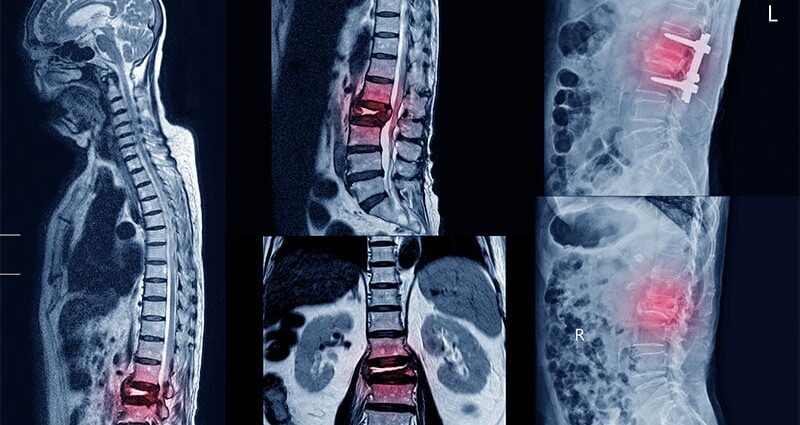

- In the overall cohort, patients with iron overload had a 55% higher risk for any osteoporotic fracture than control individuals (adjusted hazard ratio [aHR], 1.55; 95% CI, 1.42-1.68), with the highest risk observed for vertebral fractures (aHR, 1.97; 95% CI, 1.63-2.37) and humerus fractures (aHR, 1.91; 95% CI, 1.61-2.26).

- Patients with laboratory-confirmed iron overload showed a 91% increased risk for any fracture (aHR, 1.91; 95% CI, 1.73-2.10), with a 2.5-fold higher risk observed for vertebral fractures (aHR, 2.51; 95% CI, 2.01-3.12), followed by humerus fractures (aHR, 2.41; 95% CI, 1.96-2.95).